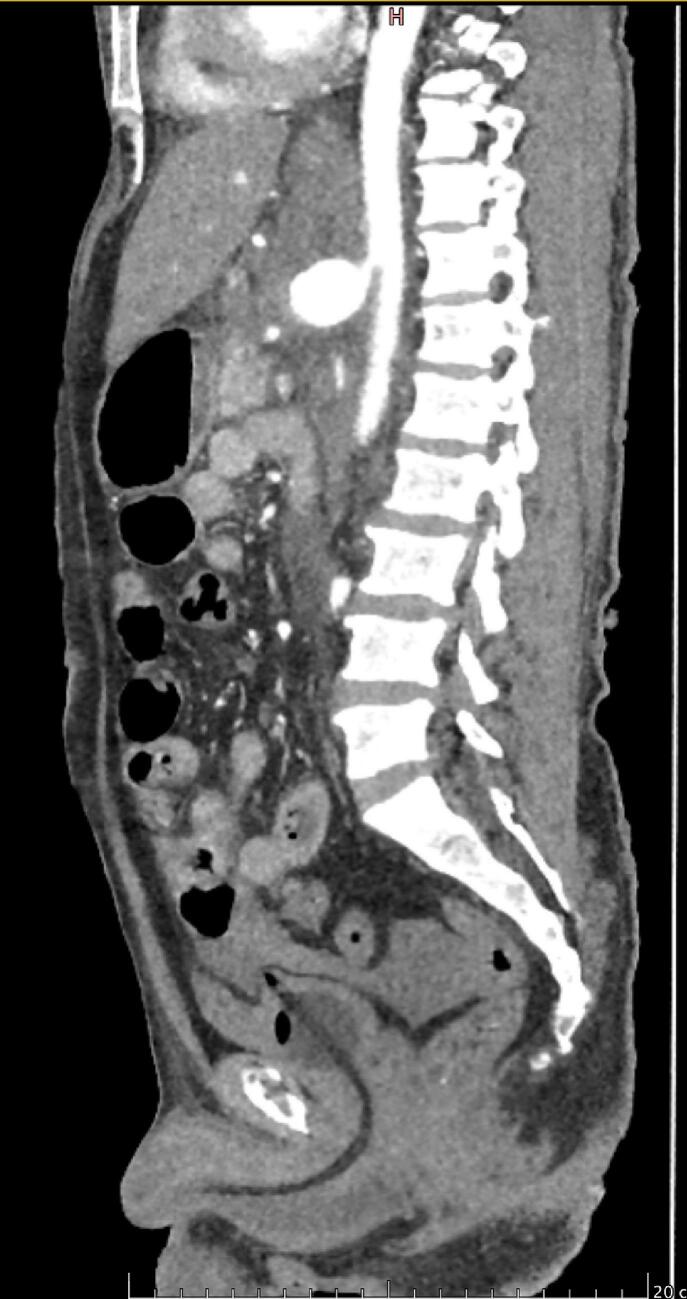

Fig. 1.

Sagittal view of CECT abdomen shows celiac artery aneurysm at T12 LEVEL.

Contrast-enhanced CT abdomen revealed a celiac artery aneurysm without any active contrast leakage, but there was a retroperitoneal hematoma (Fig. 1 and Fig. 2).